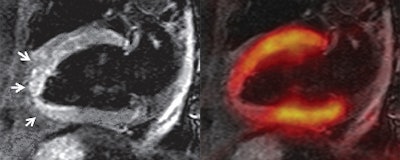

Two-chamber views show "stunned myocardium" in a 66-year-old patient with ST-elevation myocardial infarction and acute occlusion of the left anterior descending artery. Cardiac PET/MRI was performed seven days after intervention. Late gadolinium-enhanced image (top left) shows no infarction zone. Fused late gadolinium-enhanced and PET images (top right) show that tracer uptake was reduced in segments 13-15 and 17. T2-weighted MR image (bottom left) shows myocardial edema (arrows) that corresponded well with the area of reduced tracer uptake on the bottom right image. All images courtesy of Radiology.